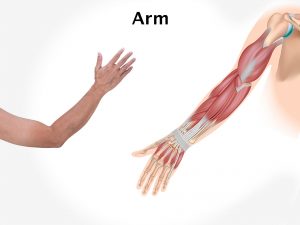

Skin receptors report a painful stimulus by sending electrical messages along sensory nerve fibers to the spinal cord. From there they travel to the brain, where the signals are interpreted as the sensation of pain. Sometimes you can feel pain in one part of the body even though the area affected is actually elsewhere. This is called referred pain, and one example is angina pain originating from oxygen starvation of the heart muscle but felt in the upper arm, shoulder and neck.